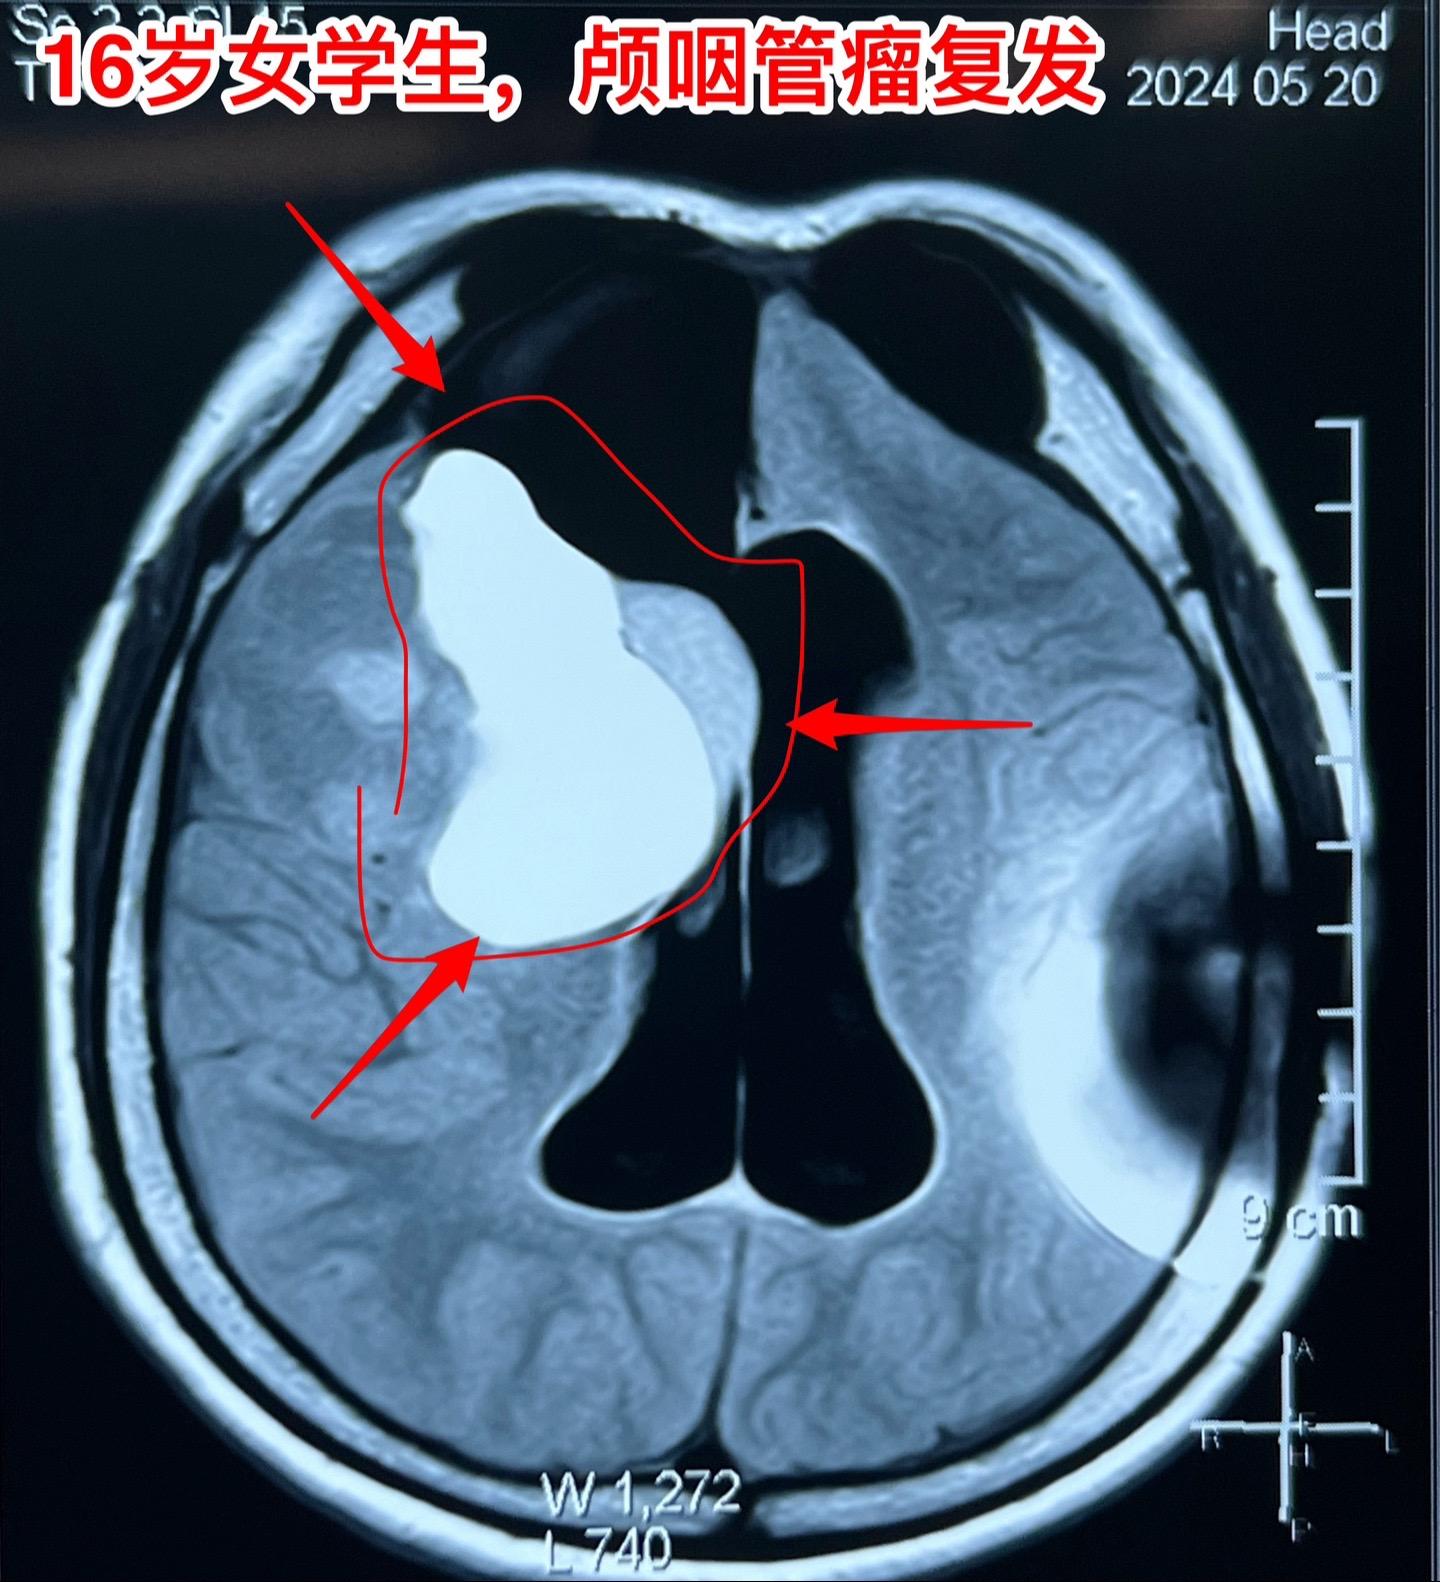

16岁女生颅咽管瘤第三次手术。第二次手术是在2013年1月。那次手术后还因脑积水作了脑室腹腔分流术。出院后能上学读书,而且内分泌方面还不错。有点遗憾的是额部手术疤痕及颅骨变形影响了病人的容貌。 这次的手术原计划在5月28日进行,因为她的生理周期突然提前了(自然的周期)故而将手术推迟到6月4日进行。肿瘤得到完全切除。 这次的肿瘤体积很大,但是还没有影响到垂体-下丘脑,可以预见,她的内分泌功能不会受到破坏。只希望她的肿瘤不再复发。内分泌

16岁女生颅咽管瘤第三次手术。第二次手术是在2013年1月。那次手术后还因脑积水作了脑室腹腔分流术。出院后能上学读书,而且内分泌方面还不错。有点遗憾的是额部手术疤痕及颅骨变形影响了病人的容貌。 这次的手术原计划在5月28日进行,因为她的生理周期突然提前了(自然的周期)故而将手术推迟到6月4日进行。肿瘤得到完全切除。 这次的肿瘤体积很大,但是还没有影响到垂体-下丘脑,可以预见,她的内分泌功能不会受到破坏。只希望她的肿瘤不再复发。颅咽管瘤内分泌